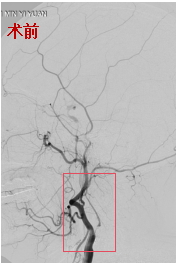

62岁女性,同样因脑梗死、左侧颈动脉狭窄入院。介入团队评估,患者颈动脉狭窄重,且远端负性重构,再灌注出血风险高,建议分期进行支架成型手术,以降低高灌注综合征发生率。两次支架成型术后,颈动脉血管重建良好,术后未发生出血等,患者平稳出院。